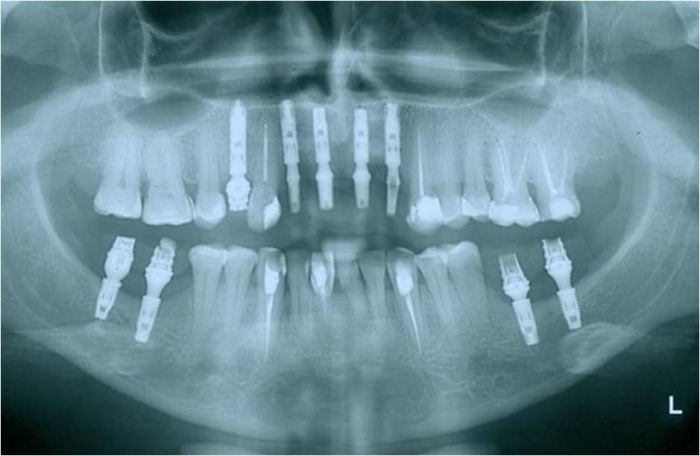

Raio x inicial